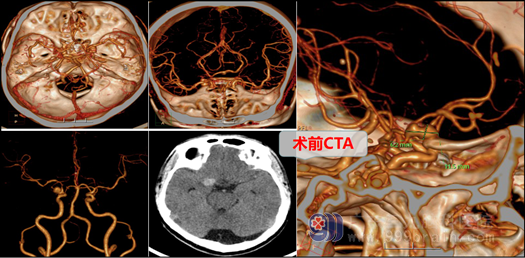

唐大哥今年44岁,平素身体健康,是家里的主要劳动力,身体也没有什么不舒服。一周前他正在工作时突发意识障碍伴左侧肢体乏力,家属紧急将其送至湛江中心人民医院就诊,经过相关检查,显示右侧后交通动脉瘤破裂出血,右侧额叶脑梗死,右侧大脑中动脉重度狭窄,右侧大脑前动脉狭窄,进行简单的对症处理后,由于病情严重且复杂,当地医院医生建议家属将其转到上级医院救治,经多方打听,家属将其转到广东最大的脑专科医院:三九脑科医院(外十科)治疗。

在完善相关检查后,外十科主任欧阳教授及冯桂栗医师向家属交待病情,说明手术的必要性和手术风险,如要好的治疗,必须在全麻下行右侧后交通动脉瘤夹闭术+脑室外引流术+去骨瓣减压术,由于患者动脉瘤出过血,又有多处动脉狭窄,手术过程困难,但欧阳教授等沉着、冷静,在显微镜下一丝不苟,仔细操作,终于取得圆满成功,将动脉瘤完全夹闭,并保持载瘤动脉通畅。术中仅输血200ml,术后复查CT未见脑梗塞等并发症,患者呼吸平顺,送重症监护室监护治疗。